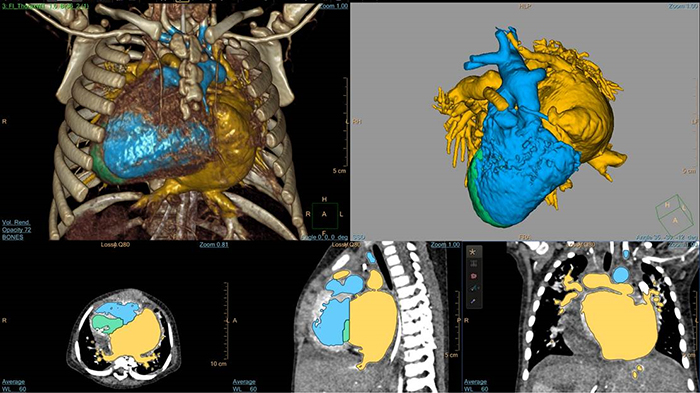

Automatic vessel analysis from rotational angiography with SmartCT

5-day old D-TGA analysis with HeartNavigator

Cardiac TrueVue photorealistic rendering with MultiVue image alignment

3D modeling with IntelliSpace Portal

EchoNavigator heart model segmentation